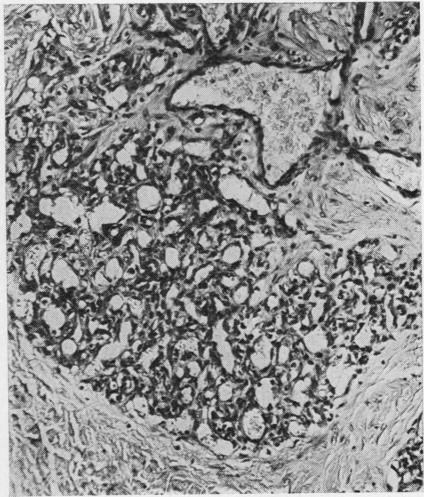

A comparison has been made between two vasoformative lesions, Kaposi's sarcoma and granuloma pyogenicum, as they are encountered in Uganda. Both are predominantly skin lesions arising in the distal extremities, may resemble each other clinically, and are widespread in their distribution in Ugandan communities. They bear a reciprocal relationship to each other as regards age and sex incidence, Kaposi's sarcoma being mainly a disease of adult males and granuloma pyogenicum a disease of immature males and females. Histologically there are many similarities between them, the essential difference being the presence of a spindle-cell sarcomatous element in Kaposi's sarcoma. The clinical behaviour reflects this difference in that granuloma pyogenicum develops quickly and appears to be self-limiting, while Kaposi's sarcoma is slowly progressive and shows much less tendency to regress. On the basis of these findings it is concluded that, although these two lesions may be completely unrelated, it is possible that both represent a response of the vasoformative elements in the skin to a similar form of initiating stimulus and that hormonal or sex-linked genetic factors determine which lesion will develop in response to this stimulus. The presence of intracytoplasmic inclusion in the tumour cells of Kaposi's sarcoma might be of significance in the histogenesis of this tumour, and of value in its histological differentiation from granuloma pyogenicum.

对乌干达出现的两种血管形成性病变——卡波西肉瘤和脓性肉芽肿进行了比较。两者主要都是发生在四肢远端的皮肤病变,在临床上可能彼此相似,并且在乌干达社区中分布广泛。它们在年龄和性别发病率方面呈反比关系,卡波西肉瘤主要是成年男性的疾病,而脓性肉芽肿是未成年男性和女性的疾病。组织学上它们有许多相似之处,本质区别在于卡波西肉瘤中存在梭形细胞肉瘤成分。临床行为反映了这种差异,脓性肉芽肿发展迅速且似乎有自限性,而卡波西肉瘤进展缓慢且消退倾向小得多。基于这些发现得出结论,尽管这两种病变可能完全无关,但两者都有可能代表皮肤血管形成成分对类似形式的起始刺激的反应,并且激素或性连锁遗传因素决定了对这种刺激会产生哪种病变。卡波西肉瘤肿瘤细胞中胞质内包涵体的存在可能对该肿瘤的组织发生具有重要意义,并且在其与脓性肉芽肿的组织学鉴别中具有价值。